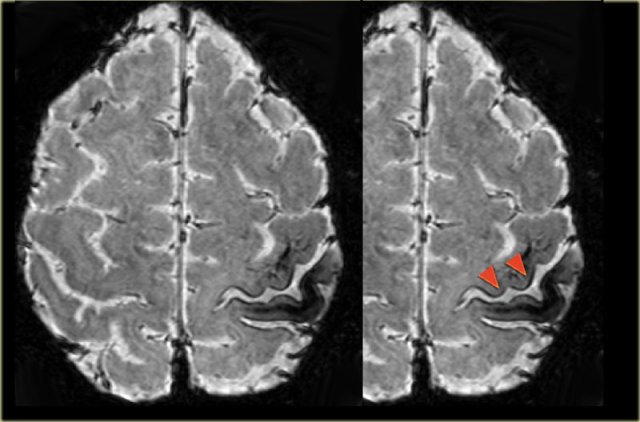

Cavernoma in the postcentral gyrus on T1WI, T2WI and SWI.

Notice popcorn appeance and blooming artefact.

Same patient.

Notice the hemosiderin coating of the precentral gyrus consistent with superficial siderosis due to prior hemorrhage of the cavernoma (red arrowheads).